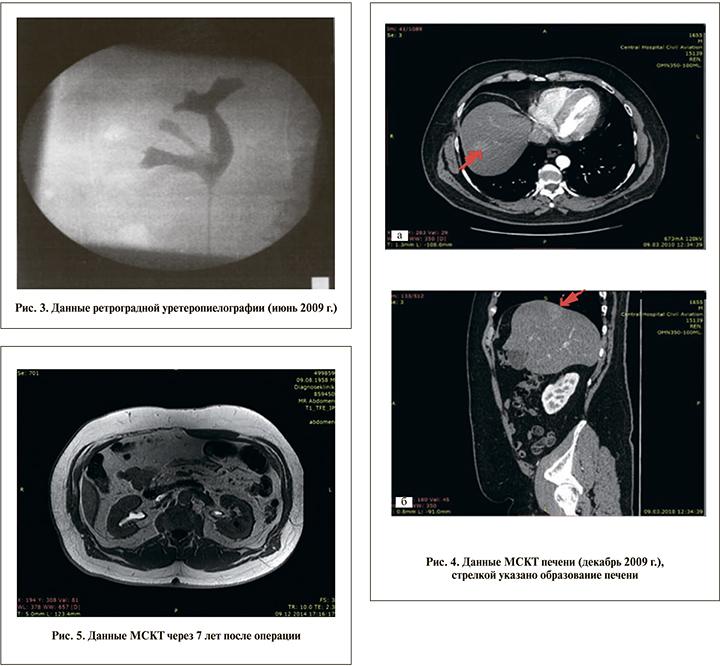

При контрольном обследовании через 3 мес., по данным УЗИ, МСКТ и диагностической цистоскопии, признаков продолжающегося опухолевого роста получено не было. Тогда же, по данным МСКТ, в VII сегменте печени выявлен участок размером около 2 см, активно накапливающий контрастный препарат (рис. 4).

В августе 2010 г. пациент обратился в Университетскую клинику г. Мюнстера (Германия) Вестфальского Вильгельм-Университета, где ему была выполнена лапаротомия с резекцией VII сегмента печени и холецистэктомия. При контрольном ПЭТ/КТ-обследовании данных за наличие метастазов не получено.

Следующее обследование проведено в 2016 г. и включало УЗИ органов брюшной полости и малого таза, МСКТ органов брюшной полости и мочевыделительной системы (рис. 5), диагностическую цистоскопию и ПЭТ. Признаков опухолевого роста или метастазирования не выявлено.